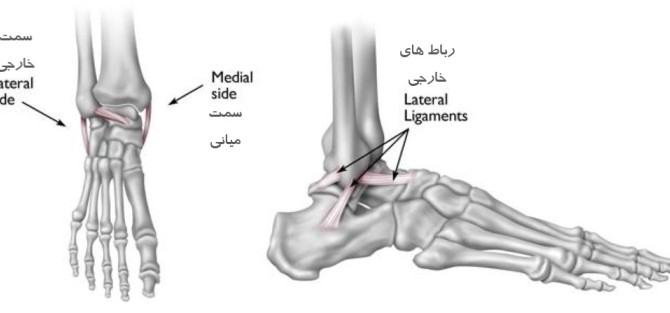

پیچ خوردگی مچ پا پیچ خوردگی مچ پا (رگ به رگ شدن) زمانی رخ میدهد که رباط های قوی ای که از مچ پا حمایت میکنند بیش از حد کش آمده و پاره میشوند. پیچ خوردگی مچ پا یک آسیب شایع است که در تمام گروه های سنی رخ میدهد. این آسیب ها بسته به میزان آسیب به رباط، بازه متفاوتی از خفیف تا شدید دارند.